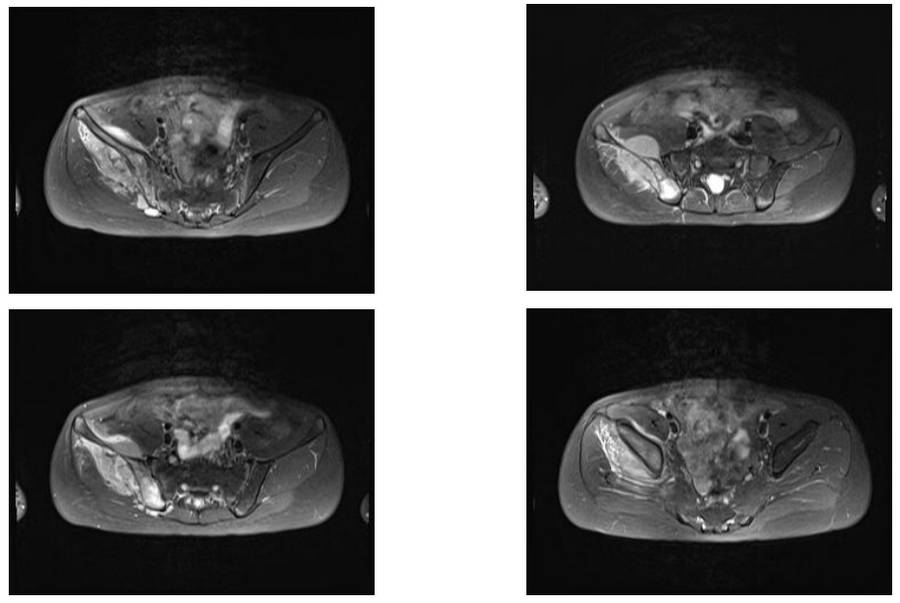

Ameliyat Öncesi: MR’da sağ ilaika kanatda yumuşak doku kitlesinin eşlik ettiği tümör dokusu görülmekte